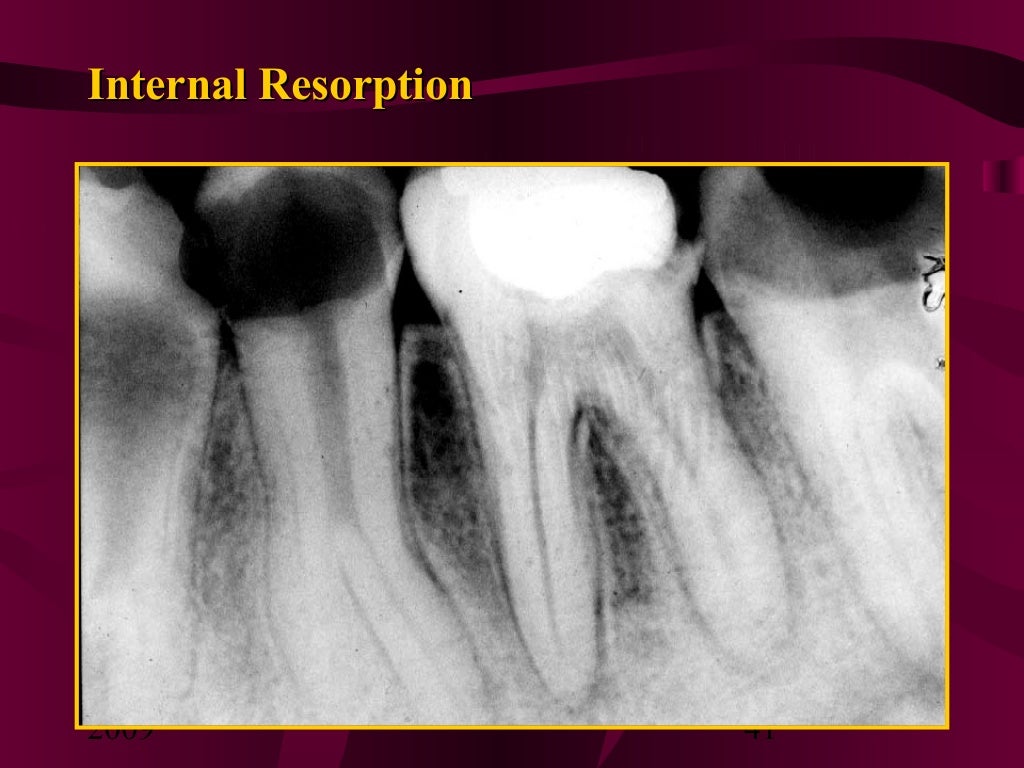

Figure 18 from Internal inflammatory root resorption the unknown Untreated Tooth Resorption Untreated dental infections can cause. To extraction if the issue is bad enough. To surgery, to remove the cells that are eating away at the tooth; tooth resorption is when the tooth structure is damaged or destroyed. external resorption is a condition that leads to broken, chipped, or damaged teeth. treatment options range from root canals, to. Untreated Tooth Resorption.